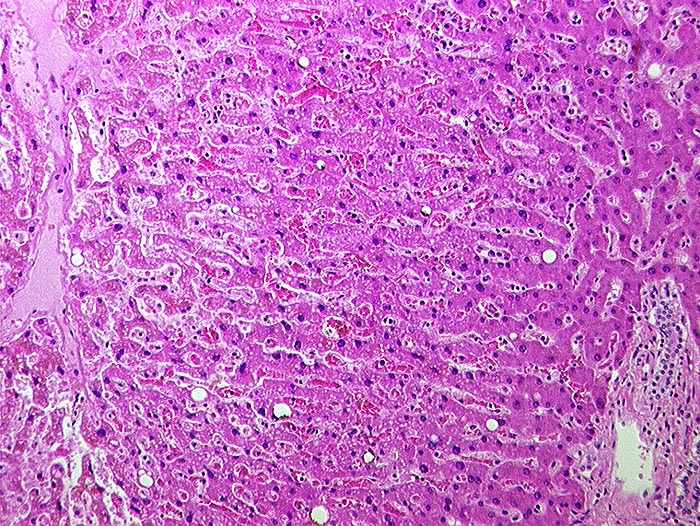

AP/ Subakute Stauung der Leber

Subakute Stauung der Leber

vaskulär / Durchblutungsstörung

Leber, Gallenwege, Pankreas

Leber

Morphologie

Virtuelles Präparat

Pathologischer Befund